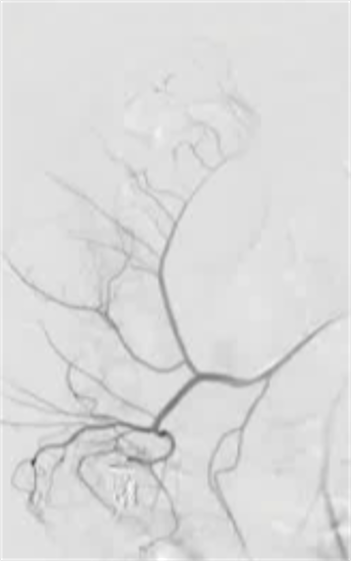

Empiric Colonic Embo Case

|

Bleeding into diverticulum

Region of bleeding tic

Post embo |